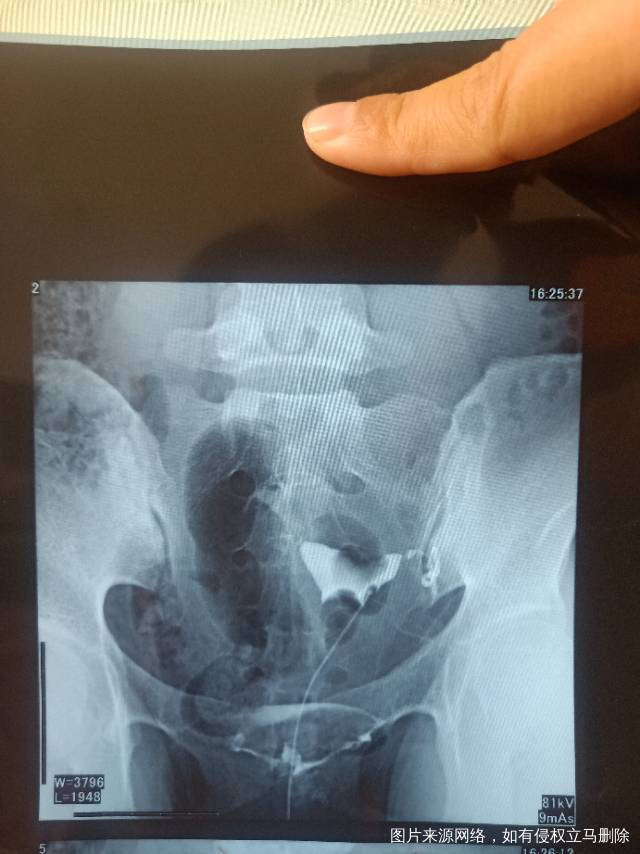

请问医生我这个造影有没有输卵管积水呀影不影响